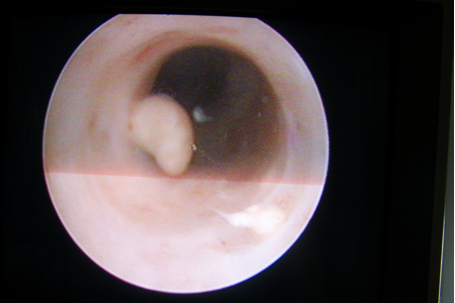

Die endoskopischen Techniken des Harntraktes wurden 1980 durch E. Perez-Castro entwickelt. Die Anwendung des starren Ureterorenoskopes in der Diagnostik und Therapie verschiedener Erkrankungen des Harntraktes führte zur ersten minimal-invasiven endoskopischen Operation des Ureters und des Nierenbeckens. In den letzten Jahren kam es zur Weiterentwicklung durch die Anwendung von flexiblen Ureterorenoskopen. Durch diese Entwicklung konnte man auch Tumore und Steine im gesamten Harntrakt in toto entfernen oder mit Laser behandeln (siehe Abbildung 4 [Abb. 4]). Ureterstenosen verschiedener Genese konnten auch endoskopisch geschlitzt oder mit Laser therapiert werden (siehe Abbildung 5 [Abb. 5]).